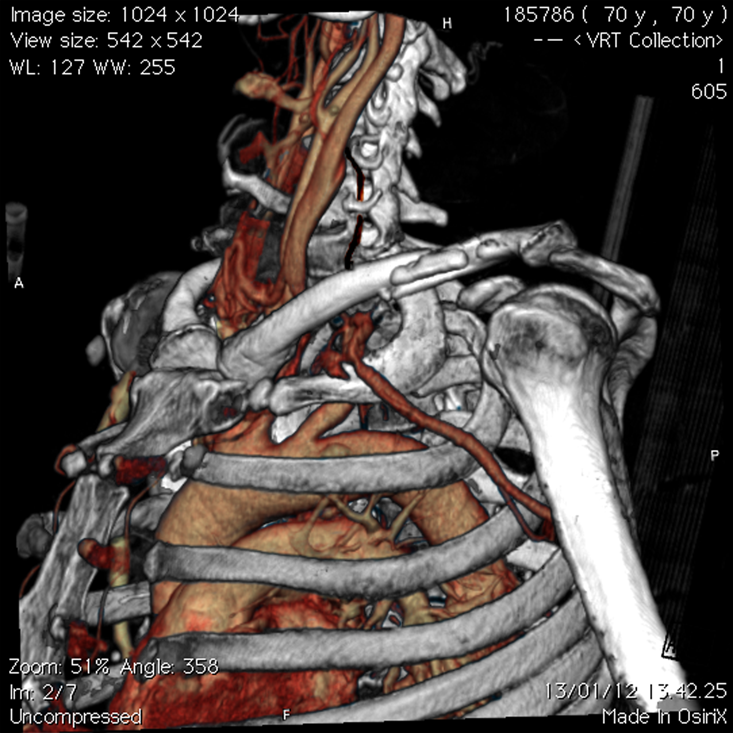

left subclavian arterial bleeding, 3 cm after homolateral vertebral artery. - CT

-

CT shows left subclavian arterial bleeding and the left midshaft clavicular fracture.